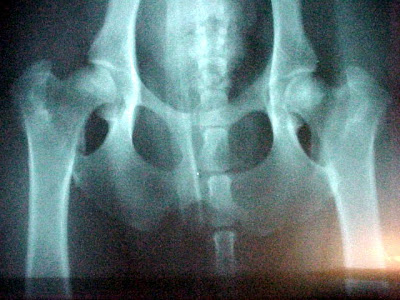

Try rating these x ray plates of Clumber hips yourself:

plate one

Plate one was officially FCI scored as D:D